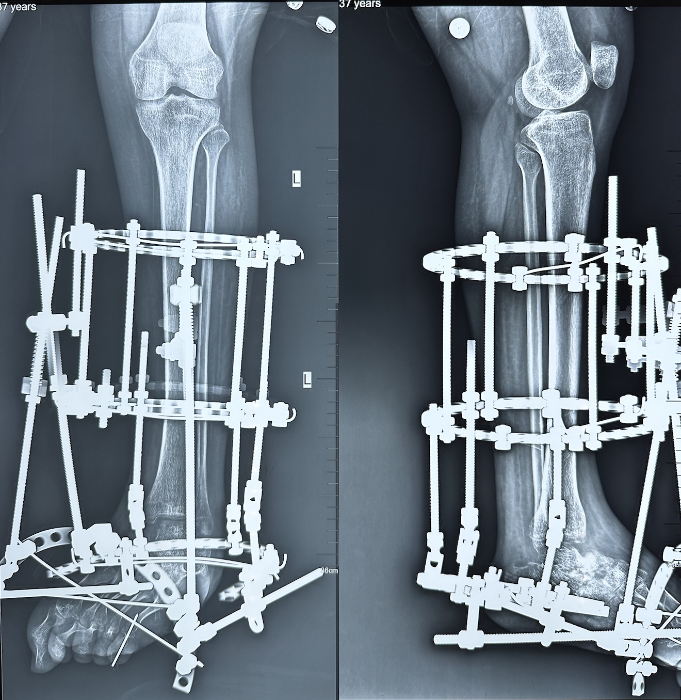

事(shì)情還(hái)要從(cóng)3個多月前說(shuō)起。王女(nǚ)士37歲,出生(shēng)時便患有左足内翻,醫學上稱爲“左側先天性馬蹄内翻足”。這是一種先天畸形,表現爲足部向内翻轉,腳掌與腳背同時着地,走路(lù)時難以保持平衡。

但(dàn)随着年(nián)齡增長,馬蹄内翻足導緻足弓增高、腿腳變形、肌肉萎縮、足跟離(lí)地、行走跛行讓她疼痛不已,并且這種情況逐漸惡化,嚴重影(yǐng)響到日(rì)常生(shēng)活。

今年(nián)7月6日(rì),姬傳磊接診後,爲王女(nǚ)士進行了全面檢查,經過反複交流病情,深入討(tǎo)論,姬傳磊團隊在全面評估王女(nǚ)士的健康狀況後,決定行左足距下關節融合、跟腱延長、肌腱松解、環形外固定架固定術(shù)。

7月7日(rì),姬傳磊團隊憑借豐富的經驗,順利完成手術(shù)。術(shù)後,姬傳磊密切關注王女(nǚ)士各項指标、生(shēng)命體(tǐ)征及傷口恢複情況,預防感染發生(shēng),并制定了詳細的康複計(jì)劃。